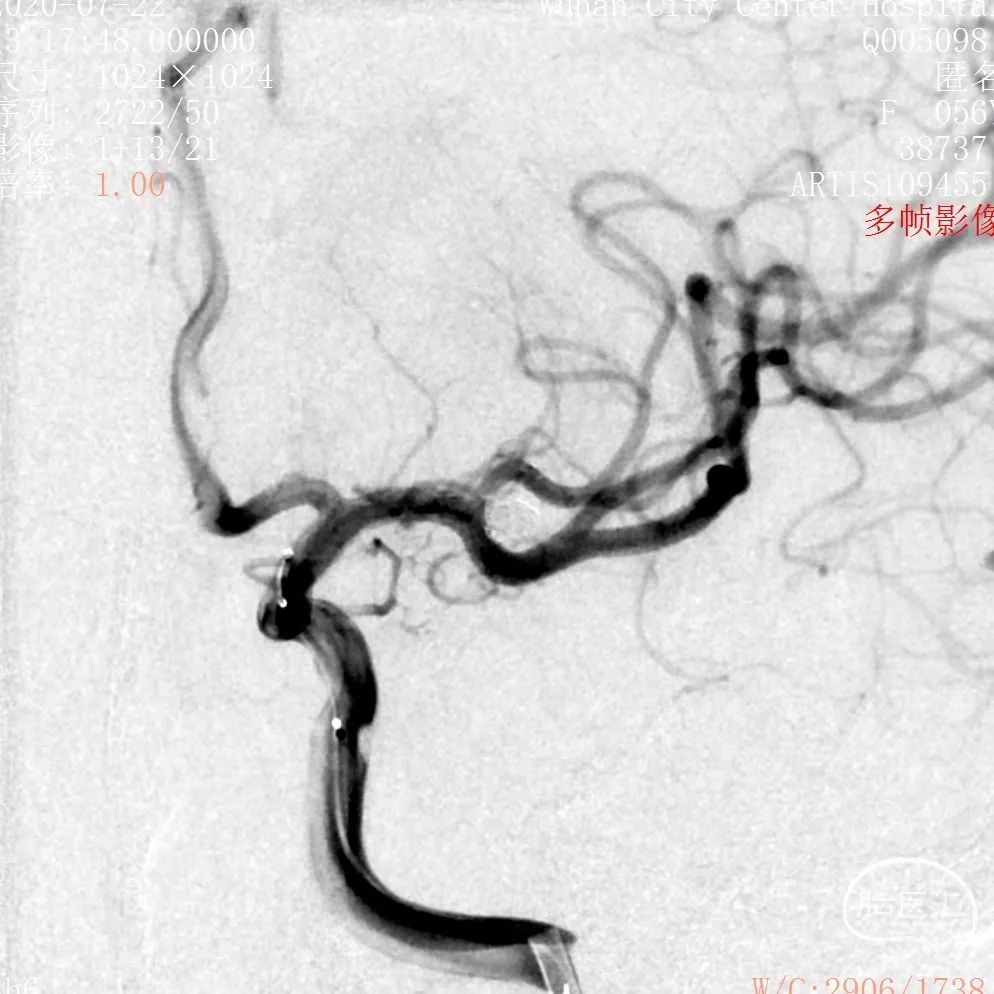

DSA 2020-07-22

3D和测量